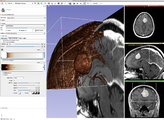

SlicerRT 0.2 has been released! SlicerRT is 3D Slicer with extensions for radiotherapy research, which is developed by SparKit project with the contributions from Slicer community.